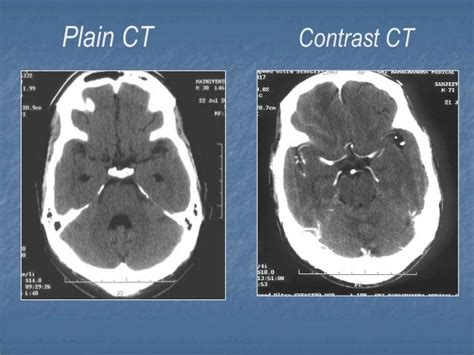

CT Scans: Contrast vs. Non-Contrast – Explained.

Unraveling CT scans: Discover the nuanced differences between contrast & non-contrast imaging. Enhance diagnostic clarity & understand what’s right for you.